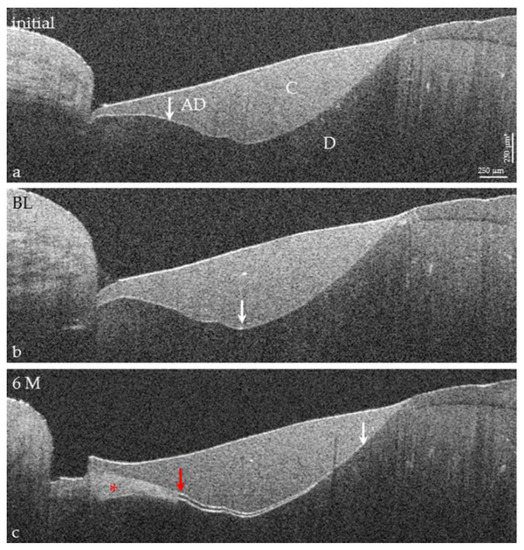

Figure 20. SD-OCT monitoring of tooth-composite bond at a cervical composite restoration (C). (a) The restoration immediately after filling the cavity in small composite increments. The composite has been homogeneously dispersed. Initially, the bright line marks an extensive adhesive defect (AD, white arrow) at dentin (D), which progressed rapidly up to the 6-month reevaluation (red arrow, the same cross-section as in image a). (b,c) Along the interface the gap is at an advanced stage (bright line, white arrow). There are no signs of secondary caries, but of ingressed material (red star, c). No distinct adhesive layer could be detected. * Vertical bar is related to refractive index n = 1.5.

Figure 20 and Figure 21 demonstrate two specific cases of gap formation between composite restoration and tooth during clinical function. Figure 20a–c show a rapid increase of bond failure at dentin over a short period of six months, while the composite-enamel bond has proven itself. In contrast, a much slower dynamic of gap progression over the longer period of 24 months is seen in Figure 21a–e. There are no signs of caries at the defective restoration margins (secondary caries). Figure 22 and Figure 23 provide an example of partial restoration loss in images and the percentage of interfacial gap formation. Within the limits of the method, the concept of restoration monitoring using OCT can be transferred onto other restoration materials.